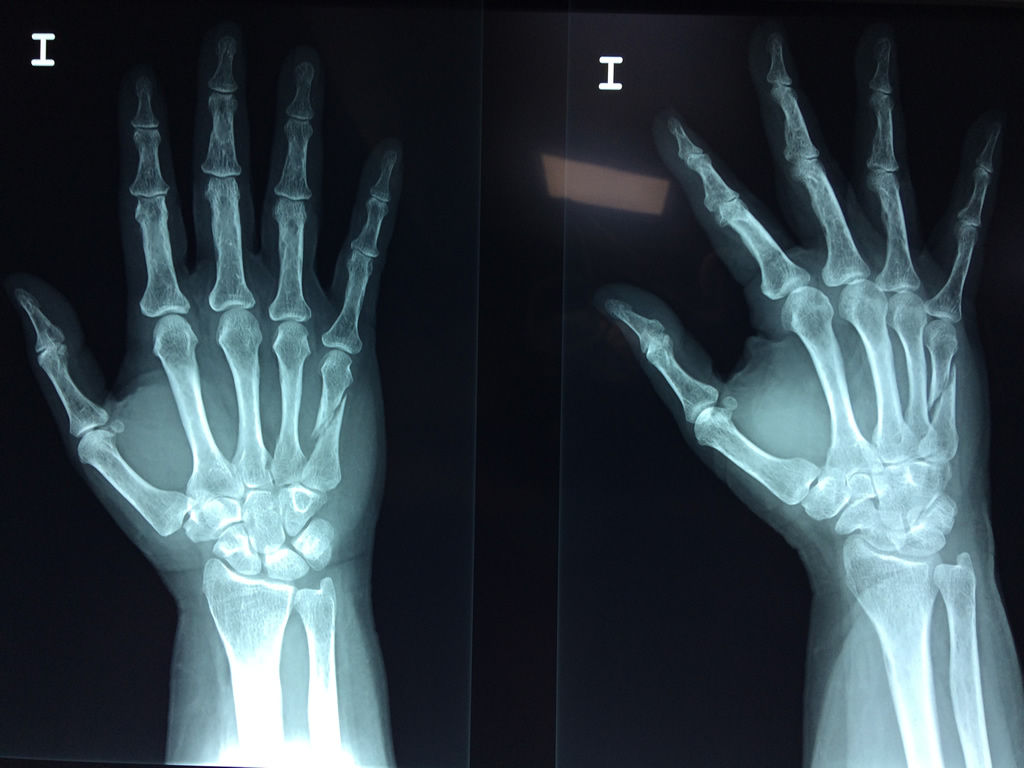

Los procedimientos más comunes en cirugía de la mano son aquellos destinados a reparar traumatismos, incluyendo lesiones de tendones, nervios, vasos sanguíneos, y articulaciones; huesos fracturados; y quemaduras, cortes, y otros daños de la piel.